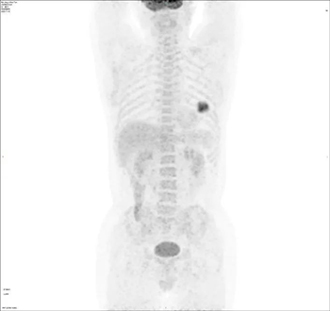

曾有这样一位患者,体检发现肺部结节,经高分辨肺部CT诊断为原发性肺癌可能,这时大夫建议他进一步做一项PET/CT检查,目的是明确肿瘤是否发生转移,为治疗方案的制定提供参考。结果如下所示:

图注:A.PET全身投影图;B.上排:PET图像;中排:CT图像;下排:PET/CT融合图像

幸运的是,PET/CT图像显示该患者除肺部肿瘤除原发灶外,没有发现淋巴结及远处转移,最终该患者直接进行了手术治疗。